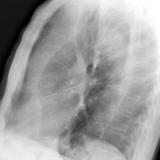

LUL Collapse Case 1 Lateral

Date: 02/19/2004

Views: 3839